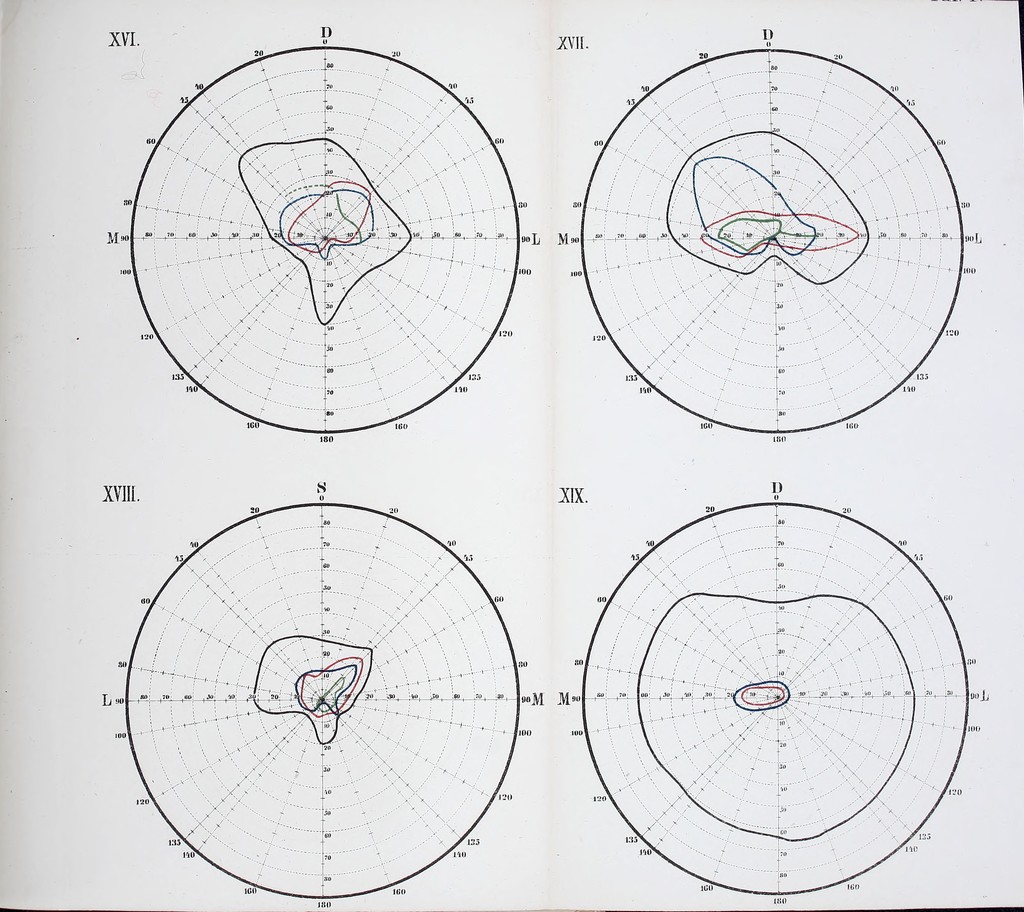

Die Lehre vom Gesichtsfelde und Seinen Anomalien : Eine physiologisch-kinische Studie / von Wilhelm Schoen.

- 1874